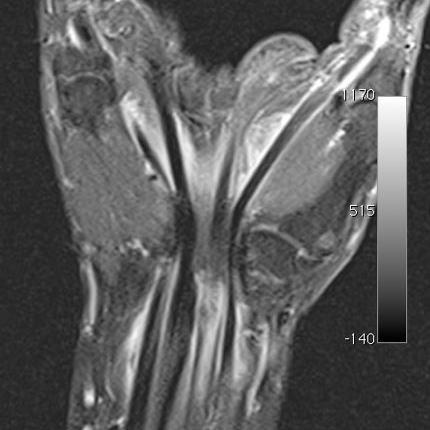

MRT Bild eines Kniegelenks in seitlicher Ansicht

Wegen ihrer hochauflösenden Darstellung von Muskeln, Sehnen, Bändern, Knochen und Knorpel ist die MRT aus der modernen Diagnostik von Erkrankungen des Bewegungsapparates nicht mehr wegzudenken.

Sehnen- und Muskelfaserrisse, Sehnen- und Schleimbeutelentzündungen, Knorpelschäden an den Gelenken, Knochenbrüche, Verschleißerkrankungen und jegliche Entzündungen und Tumoren des Stütz- und Bewegungsapparates lassen sich vorzugsweise mit der MRT abbilden.